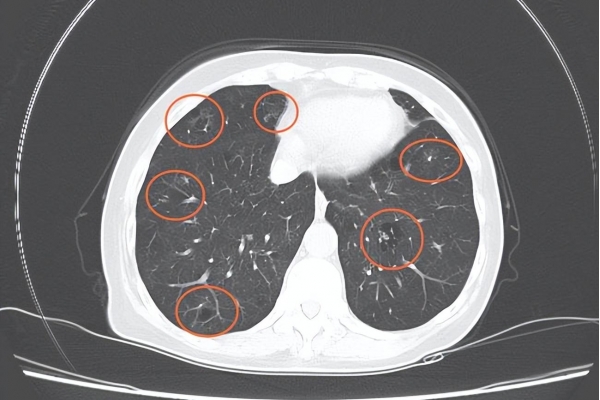

2. 肺结节:不是所有"磨玻璃"都要处理

很多人在体检中查出"磨玻璃影",吓得不轻。

但其实,肺结节≠肺癌。

磨玻璃结节是一种在低剂量CT中高频出现的影像表现,形态像一团薄雾,大多数是良性的,有些甚至是炎症后的残留改变。

《中国肺结节管理专家共识》指出:直径<6mm的肺结节,尤其是孤立的单个结节,恶变率极低,建议观察即可,无需穿刺、手术或药物干预。

只有当结节直径>8mm,或者短期内明显增大,才需要进一步检查包括PET-CT、穿刺等。

切记:过度治疗肺结节,不仅不会更安心,反而可能带来不必要的风险。